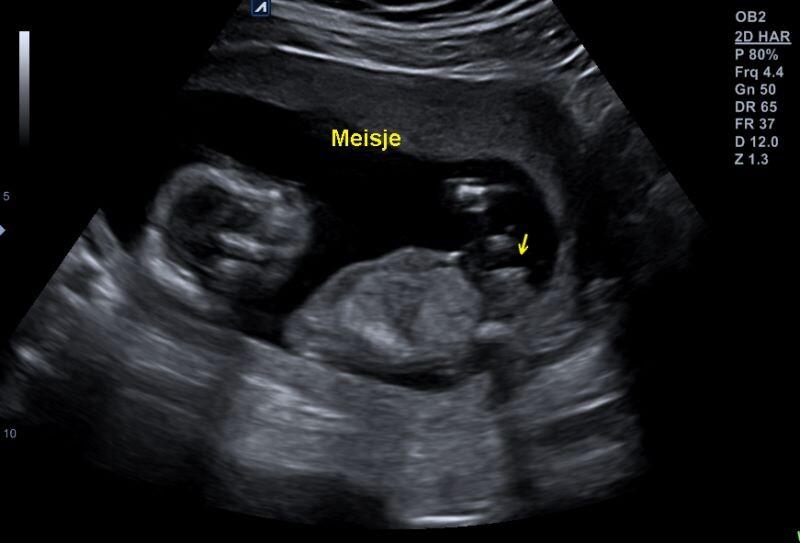

Bij binnenkomst werden wij vriendelijk begroet en ik moet zeggen dat ik mij er gelijk op mijn gemak voelde. De sfeer was ontspannen en huiselijk. Aangezien wij het liefst pas het geslacht wilde weten op zaterdag met de gehele familie, draaide die meneer het scherm weg. Binnen vijf minuten vertelde hij dat hij het geslacht duidelijk had gezien. Daarna zette hij het scherm aan en konden wij zelf ook onze kleine spruit bewonderen. Uiteraard zorgde hij ervoor dat het geslacht niet in beeld kwam tijdens de rest van de echo.

Ik dacht zelf steeds dat het een meisje zou worden, maar werd erg aan het twijfelen gebracht door zijn opmerkingen: “Het is echt een doerak” en “jeetje wat een boef”. Vanaf dat moment was ik helemaal blanco haha. Tiemen zei vanaf het begin af aan al steeds het wordt een jongen. Ook na deze echo bleef het voor ons dus spannend. Wij kregen aan het einde een envelop mee voor de bakker en een envelop mee voor onszelf, dichtgeplakt met een foto van het geslacht. Ik kocht ook een usb stick waar de gehele echo opgenomen was. Dit was slechts € 7,50 en ik vond het wel zo leuk dat op die manier de aankomende opa’s, oma’s, ooms en tantes dit ook terug kunnen zien.

Later hebben wij de dichte envelop er nog even bij gepakt. Ook daarin stond het: wij krijgen een meisje! Alhoewel het mij niets uit maakte of ik een jongen of een meisje zou krijgen, vind ik het toch wel leuk dat mijn eerste voorgevoel toch echt aangaf een meisje. Dit terwijl ik vroeger (voor ik zwanger werd) altijd dacht dat ik eerst een jongen zou krijgen.